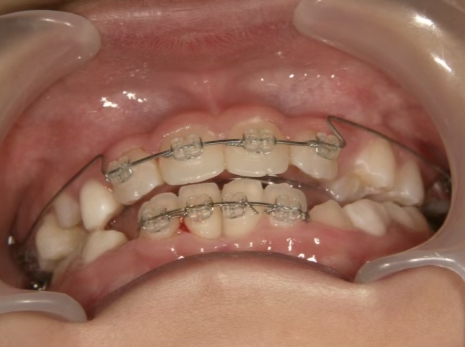

治療中③ 小4:9y10m

咬合治療用モノブロック装置(筋機能的咬合誘導装置)スタート

*就寝時に使用するモノブロック装置(筋機能的咬合誘導装置)